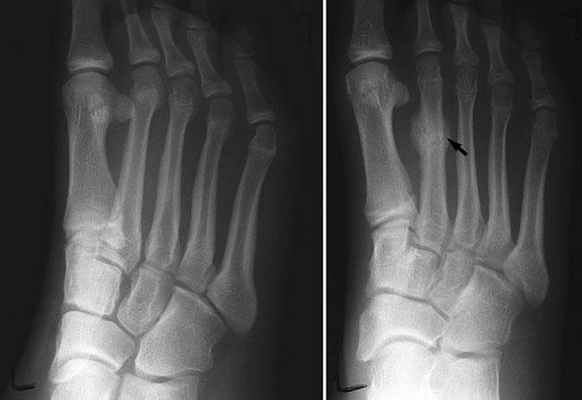

Рекомендуется выполнение стандартных рентгенограмм, но они могут не показывать никаких изменений до тех пор, пока спустя 2–3 недель после травмы не образуется костная мозоль. Часто для ранней диагностики необходимо сканирование костей с внутривенным введением технеция дифосфоната. Женщины со стрессовыми переломами могут страдать остеопорозом, им следует выполнить двухэнергетическую рентгеновскую абсорбциометрию Диагностика Остеопороз – прогрессирующее метаболическое заболевание кости, при котором происходит снижение ее минерализации (массы костной ткани на единицу объема), сопровождающееся нарушением ее структуры. Прочитайте дополнительные сведенияЛечение стрессовых переломов

Если после первичной оценки есть подозрения на стрессовый перелом, терапевту следует направлять пациента на диагностику для подтверждения или опровержения диагноза. Рентгеновские снимки обычно используются для диагностики стрессовых переломов, несмотря на плохую чувствительность. Стрессовые переломы обычно не проявляются на рентгенограмме в течение 2 – 6 недель после травмы; когда они становятся видимыми, появляются в виде полос просветления и могут иметь кортикальное уплотнение. Остеосцинтиграфия является наилучшей диагностической визуализацией стрессовых переломов (переломы заметны во 2-3 день после травмы).